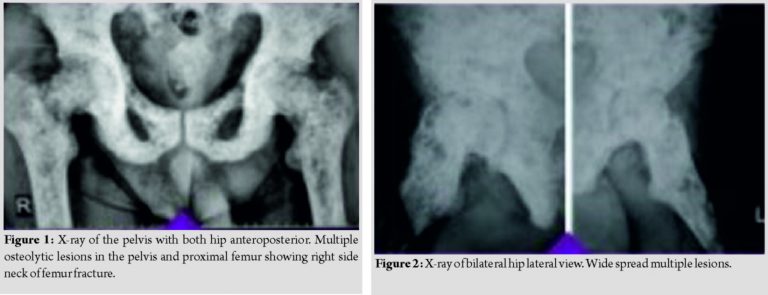

The patient then visited our tertiary center where the thorough skeletal survey was done, which showed involvement of pelvis (Fig. 1 and 2), spine (Fig. 3), and appendicular skeleton(Fig. 4 and 5) as well. The lesions were osteolytic, small, multiple, of varied sizes involving the whole of the involved bone, rather symmetrically (Fig. 6).

The X-ray with which the patient presented showed superior cortical breach in the femoral neck, but on traction X-ray, the pathological trans-cervical neck femur fracture was noted (Fig. 1). Differential diagnoses considered were metastasis, osteopoikilosis, and multiple myeloma.